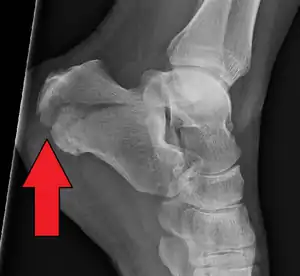

Calcaneal fractures are categorized as intra-articular or extra-articular on the basis of subtalar joint involvement. Intra-articular fractures are more common and involve the posterior talar articular facet of the calcaneus. The Sanders classification groups these fractures into four types based on the location of the fracture at the posterior articular surface. Extra-articular fractures are less common and may be located anywhere outside the subtalar joint.[13] Extra-articular fractures are categorized depending on whether the involvement of the calcaneus is anterior (Type A), middle (Type B) or posterior (Type C).[15]

Extra-articular fractures include all fractures that do not involve the posterior facet of the subtalar joint.

- Type A involve the anterior calcaneus

- Type B involve the middle calcaneus. This includes the sustentaculum tali, trochlear process and lateral process.

- Type C involve the posterior calcaneus, the posterior tuberosity and medial tubercle included.